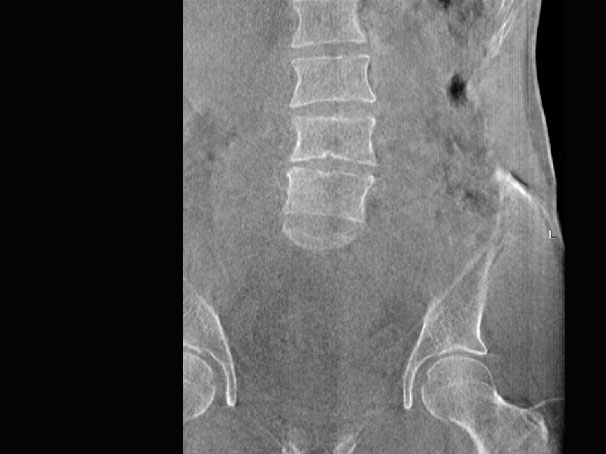

· 补位CT,提供负重位三维影像

· 引领普放走向三维精准诊断时代

填补常规CT/MR空白

助力术前规划和术后评估

腰椎